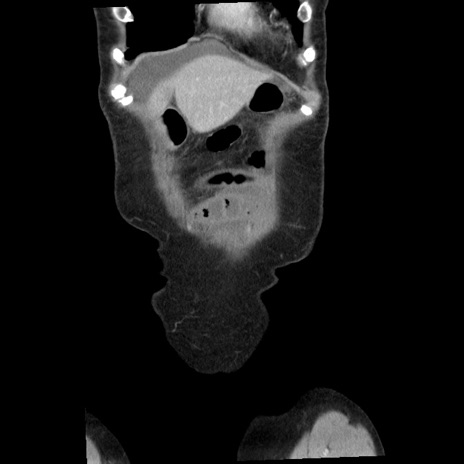

横断像

矢状断像